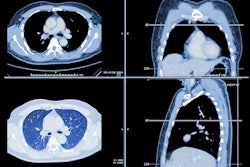

Median Technologies is highlighting clinical results that show that its iBiopsy lung cancer screening deep-learning algorithm has a sensitivity of 93.1% and a specificity of 96.2% for characterizing lung nodules on low-dose chest CT.

The results are based on a study that included 1,737 patients and 16,249 lung nodules from the National Lung Screening Trial. The training set for iBiopsy consisted of 1,239 patients with 11,676 nodules, and the test set included 498 patients with 4,573 nodules.

The iBiopsy algorithm showed a sensitivity of 93.1% for identifying stage 1 lung cancers and a specificity of 96.2% for identifying stage I, IA, and IB nodules.